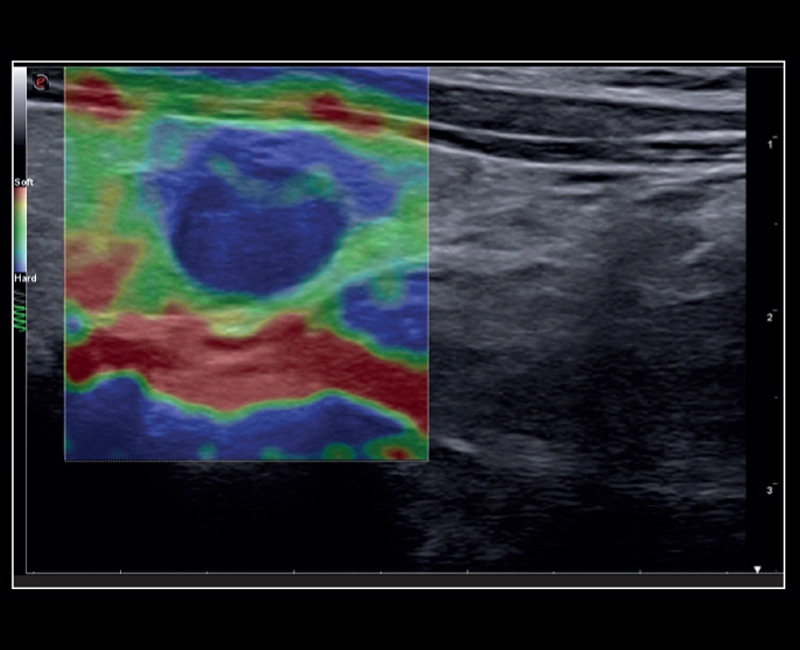

MyLab™C25 - ElaXto in breast

MyLab™C25 - ElaXto in breast